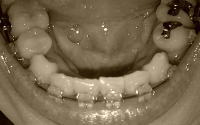

以下、画像です。

061129c.jpg 今日

060913a.jpg 7月14日

060913b.jpg 9月13日

061129b.jpg 今日